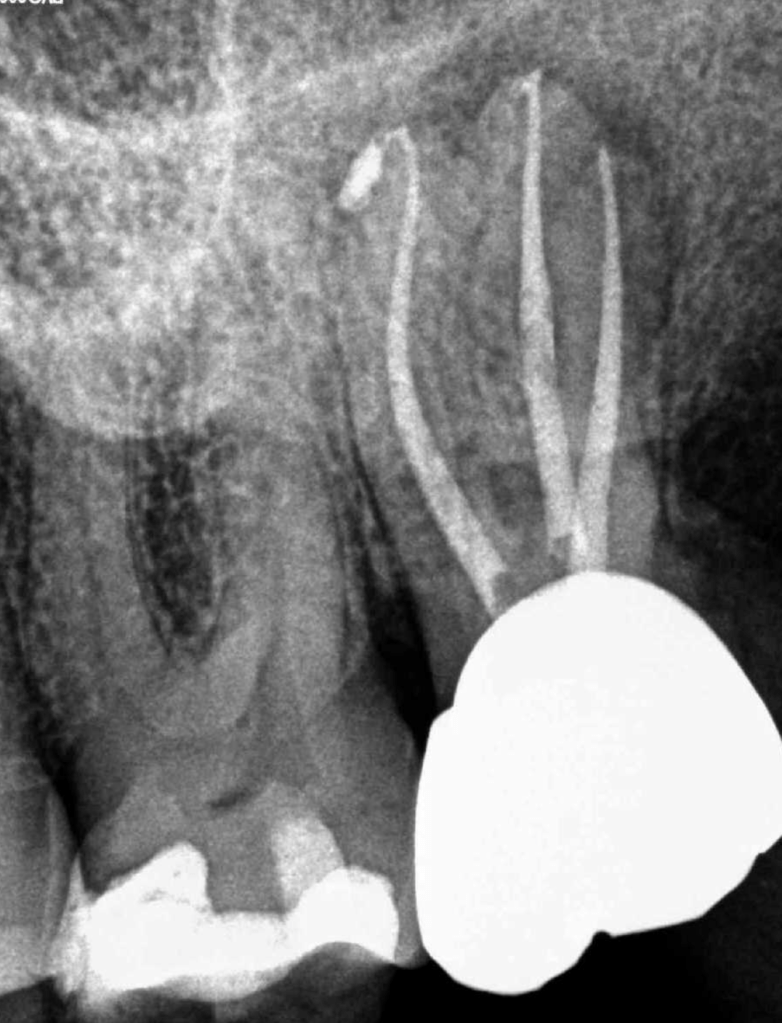

Premolar calcificado lesion

CALCIFICADOS